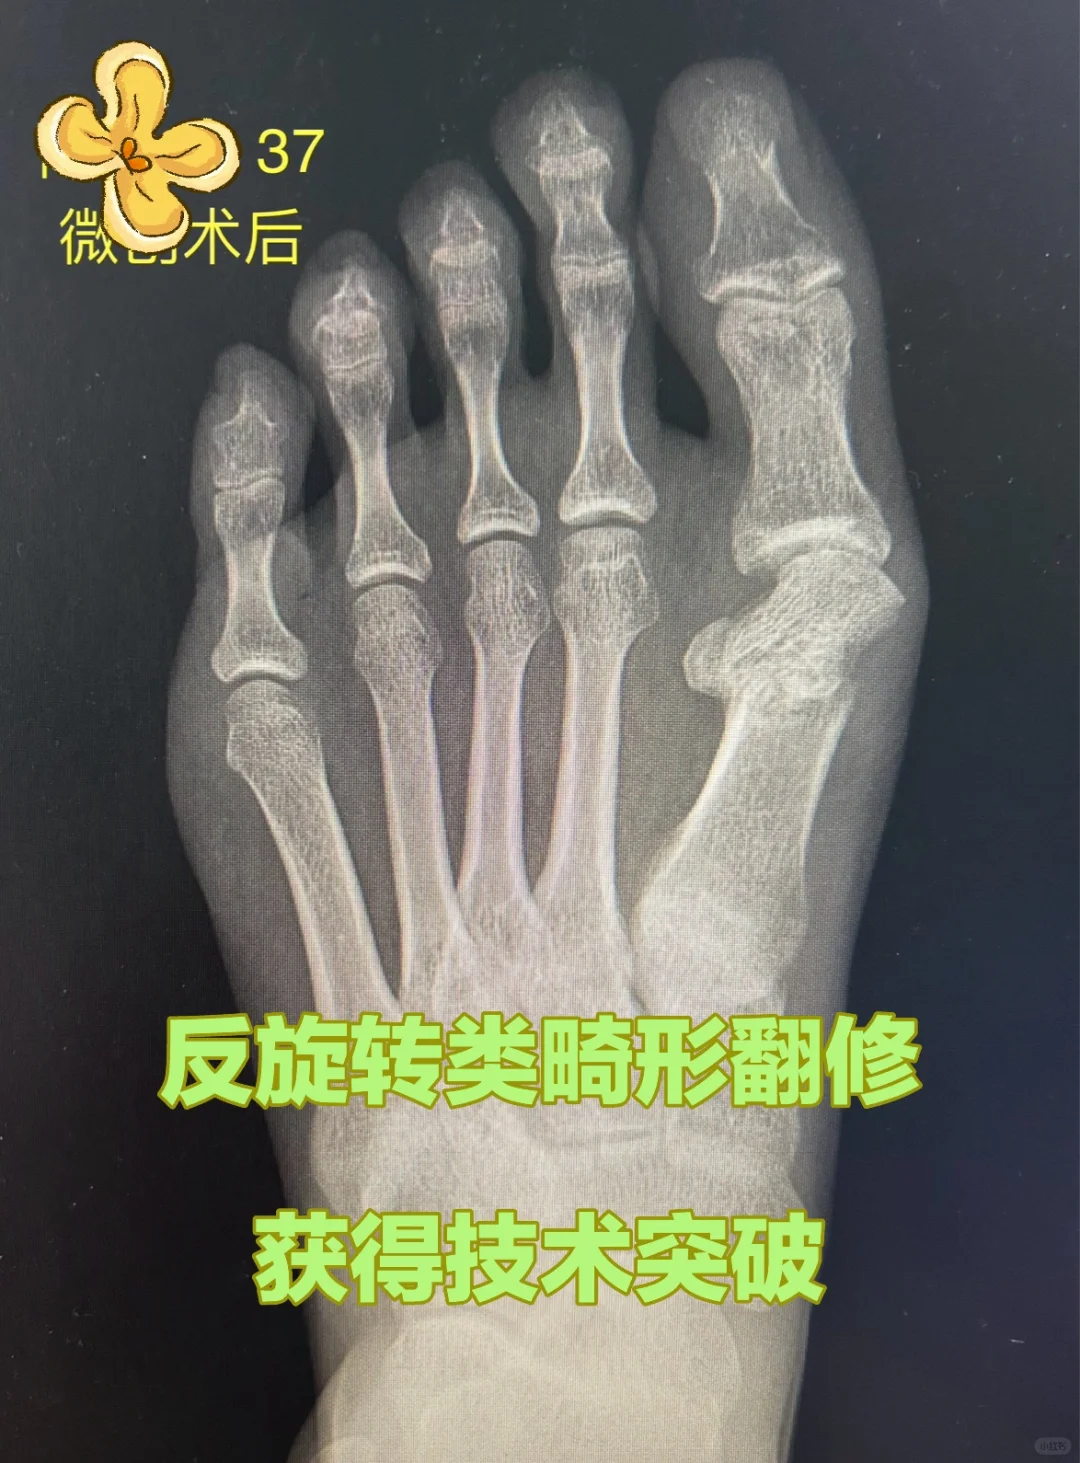

微创术后II型畸形翻修……获得研究突破